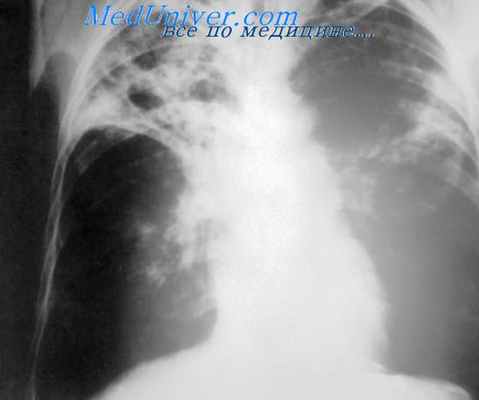

Возникающие при заражении патологические изменения в органах и клинические проявления болезни весьма разнообразны и объединяются понятием «микобактериозы». Penso, предложивший этот термин в 1959 г., различает 4 основные клинические формы процесса: бронхо-легочную, почечную, лимфожелезистую и кожную. Наиболее частая из них — бронхо-легочная — проявляется в виде хронической пневмонии, пневмокониоза, бронхоэктатической болезни, плеврита, но чаще всего протекает под видом фиброзно-кавернозного, хронического диссеминированного, реже очагового и инфильтративного туберкулеза легких). Клинически отличить эти формы микобактерио-зов от специфического туберкулезного процесса часто трудно.

Кашель и откашливание распространены, часто связаны с утомляемостью, потерей веса и небольшой лихорадкой. Течение заболевания может медленно прогрессировать или быть устойчивым в течение длительных периодов. Дыхательная недостаточность и постоянное кровохарканье может прогрессировать. Фиброзно-очаговые инфильтраты при рентгенографии грудной клетки такие же, как и при легочном туберкулезе, но реинфекция имеет тенденцию быть тонкостенной, и плевральные выпоты наблюдаются. Так называемые инфильтраты «дерево с набухшими почками», обнаруживаемые при КТ грудной клетки, также характерны для болезни, обусловленной MAC.